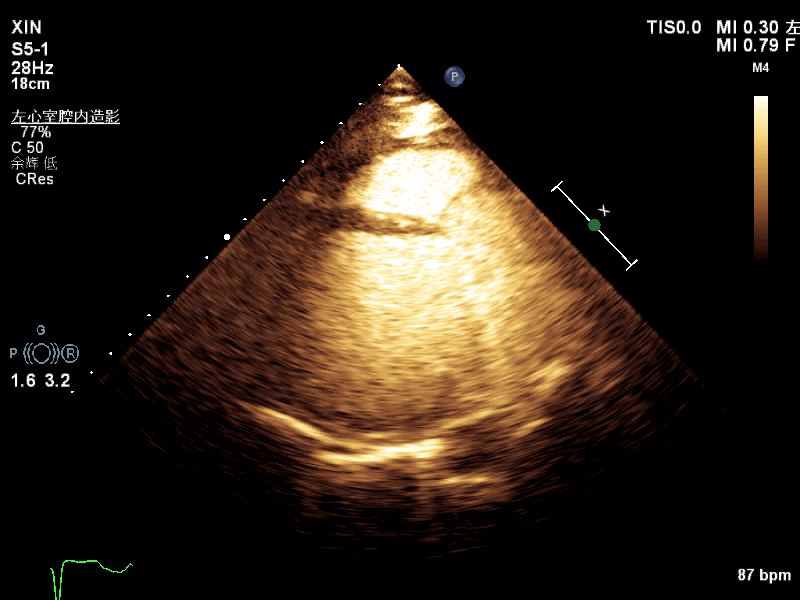

【特色診療】超聲心動圖及左心聲學(xué)造影評估化療藥物相關心髒毒性

鄭曉偉 林長(cháng)裕 普甯現代醫院